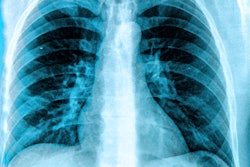

- Is chest x-ray about to be rendered obsolete by chest CT scans? Or will integration with AI allow chest radiographs to hold their own? Those questions were answered in another session.

Aside from our ECR coverage, it appears that researchers are calling for more “real-world” studies of AI algorithms designed for interpreting chest x-rays. Recently, a group in Spain tested a product called ChestEye (approved in the European Union in 2019) and found it provided less than what’s required for clinical implementation.